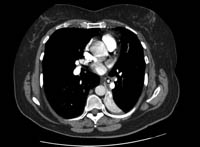

Uma radiografia torácica deve ser obtida no início da avaliação da tosse crônica.[38] Embora não seja diagnóstica das causas mais comuns, os achados podem facilmente desviar a avaliação para causas de maior gravidade como doenças pulmonares estruturais. Eles incluem câncer pulmonar, fibrose pulmonar, tuberculose, bronquiectasia, pneumonia, aspiração e sarcoidose.[Figure caption and citation for the preceding image starts]: Radiografia torácica mostrando hiperinsuflação em paciente com DPOC. A hiperinsuflação é causada pelo componente de enfisema na DPOC, em vez da bronquite crônica subjacente aos sintomas da tosseDo acervo pessoal do Dr. M. A. Sharifabadand, SUNY na Stony Brook School of Medicine, Departamento de Medicina Pulmonar e Intensiva, Mineola, Nova York, e Dr. J. P. Parsons, The Ohio State University Medical Center, Columbus; usado com permissão [Citation ends].

TC de alta resolução do tórax para procurar bronquiectasia (a qual nem sempre promove tosse produtiva), aspiração de corpo estranho, fibrose pulmonar ou outra doença pulmonar estrutural (que pode não aparecer bem na radiografia torácica). A doença pulmonar supurativa crônica é diagnosticada nos pacientes com sintomas clínicos de bronquiectasia, mas sem evidência radiográfica de bronquiectasia.[50] A TC também pode indicar a presença de um aneurisma aórtico ou um divertículo de Zenker. A expectativa quanto ao rendimento diagnóstico da TC do tórax em um paciente com tosse crônica e radiografia torácica normal é de que seja baixo.[3][Evidência C] Não há evidências de alta qualidade para apoiar o uso da TC de tórax na avaliação inicial dos pacientes com tosse crônica.[38]

[Figure caption and citation for the preceding image starts]: Tomografia computadorizada (TC) do tórax com presença de anel de sinete à esquerda em paciente com bronquiectasiaDo acervo pessoal da Dra. S.M. Bhorade, University of Chicago Medical Center [Citation ends].

[Figure caption and citation for the preceding image starts]: Tomografia computadorizada (TC) do tórax com vias aéreas dilatadas e espessadas e um padrão de árvore em brotamento periférico em paciente com bronquiectasiaDo acervo pessoal da Dra. S.M. Bhorade, University of Chicago Medical Center; usado com permissão [Citation ends].